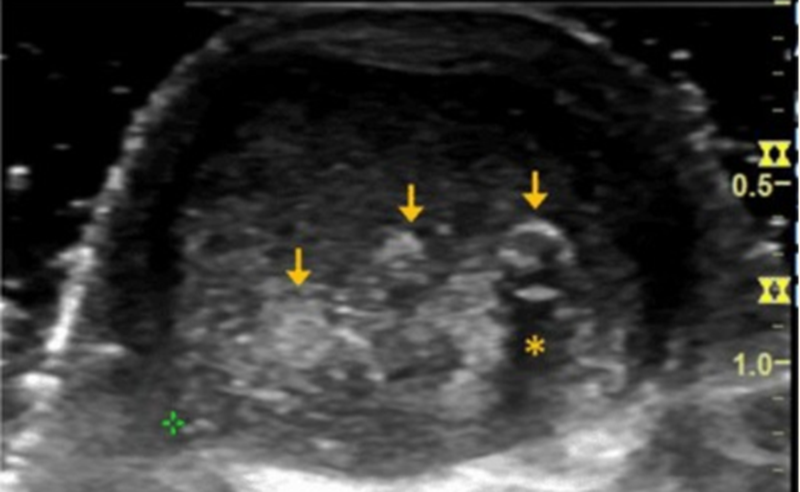

跟腱焦磷酸钙沉积病